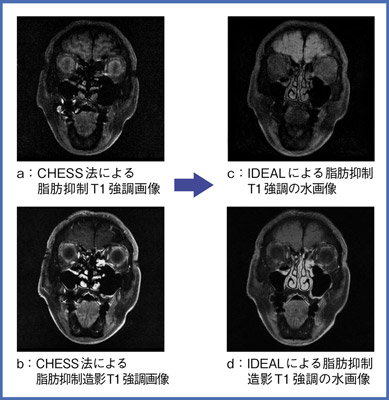

Vol 6 Idealの有用性について